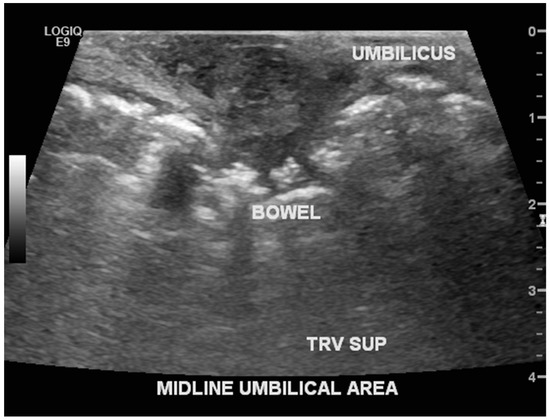

2.1. Case 1

2.2. Case 2